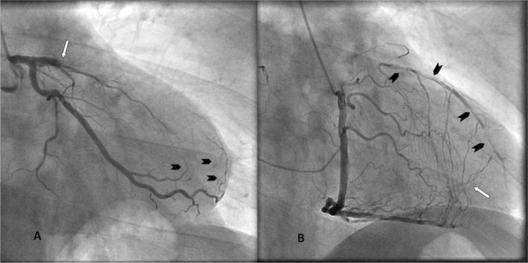

Despite the remarkable advances in revascularization strategies made during the last decade, a significant proportion of patients are excluded from either percutaneous coronary intervention or coronary artery bypass grafting because of unsuitable coronary anatomy. Diffuse severe coronary artery disease, small vessel caliber, chronic total occlusions, or extremely calcified vessels are frequent reasons for deferring revascularization with either percutaneous coronary intervention or coronary artery bypass grafting. We present a case concerning a middle-aged asymptomatic patient who was treated successfully with percutaneous coronary intervention due to a chronic total occlusion lesion of the left anterior descending artery. Coronary angiography is an inadequate method for the estimation of the burden of atherosclerotic disease in an artery fed by collaterals. Assessment of any residual antegrade flow, and ipsilateral and contralateral collateral filling of the segments distal to the occlusion with invasive or noninvasive techniques, could affect the appropriate decision-making by physicians.

尽管在过去十年中血管重建策略取得了显著进展,但由于冠状动脉解剖结构不合适,仍有相当一部分患者被排除在经皮冠状动脉介入治疗或冠状动脉旁路移植术之外。弥漫性严重冠状动脉疾病、小血管管径、慢性完全闭塞或血管极度钙化是推迟经皮冠状动脉介入治疗或冠状动脉旁路移植术进行血管重建的常见原因。我们报告一例中年无症状患者,该患者因左前降支慢性完全闭塞病变成功接受了经皮冠状动脉介入治疗。冠状动脉造影对于评估由侧支循环供血的动脉中动脉粥样硬化疾病的负担是一种不充分的方法。采用侵入性或非侵入性技术评估任何残余的顺行血流以及闭塞远端节段的同侧和对侧侧支循环充盈情况,可能会影响医生做出恰当的决策。